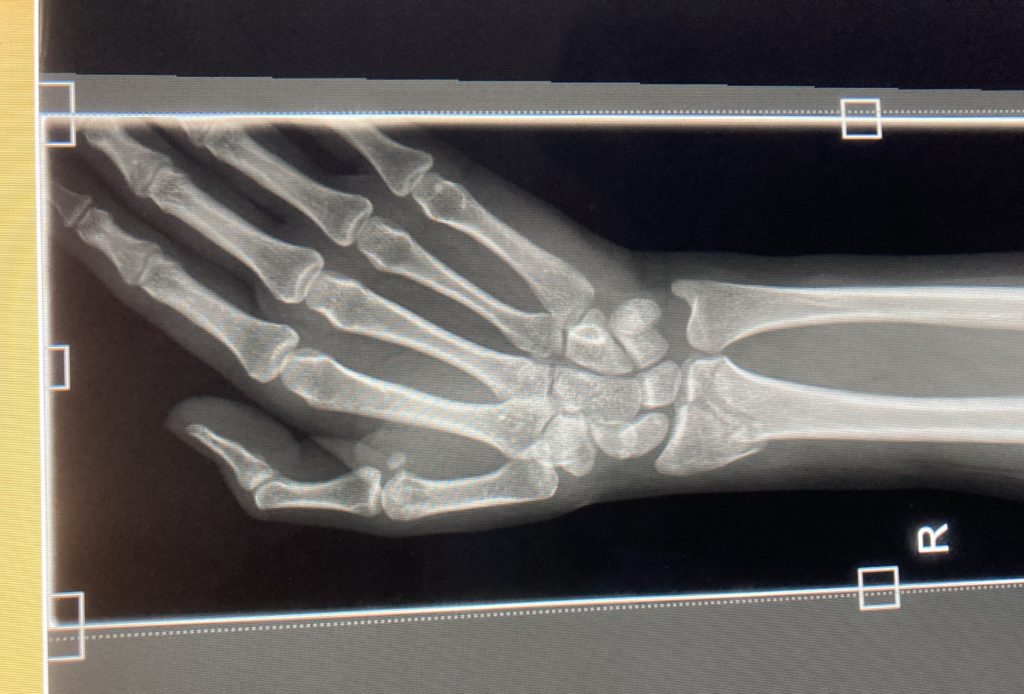

レントゲンを撮る際に、看護師さんに「スマホ持ってる?」と聞かれてレントゲン室だからスマホ持ってちゃいけないのかと思ってすぐ渡したのですが、看護師さんが「カメラ開いて」と言いました。その後パソコン上に表示されたレントゲン写真を私のスマホで撮っておいてくれました。優しすぎる…。

レントゲンを撮った後、私はその場にしばらく放置され、看護師さんとおじいちゃんのお医者さんがパソコンを見て何やらずっと話していました。2人だけで話してる時間が長かったので、私の方から2人に「折れてます…?」と聞いたところ、看護師さんが神妙な顔で、黙って(折れてるわよ…)と、こちらにうなずき返してきました。泣く。

後で写真を確認すると、親指側のほうの手首の骨が折れて、ちょっと横に飛び出してるような感じになっていました。マジで痛い…

その後スキースノボを楽しんでいた他のホストファミリーたちも戻ってきて、その時の状況を話したり、レントゲンの写真を見せて「うわー痛そー」と言われたり、後はいっぱい慰めてもらいました。私の日本の家族に今の状況をLINE通話で伝えたりもしました。